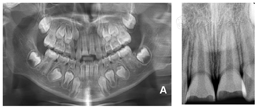

X线曲面断层片及根尖片显示(图1):11、21髓腔宽大,根管壁平行,牙根发育Nolla9期,牙周膜间隙均匀,根尖孔未闭合。未见关节及颌骨骨折等异常影像。